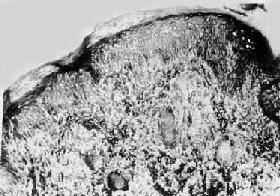

图18-17 结核样型麻风 真皮内有主由类上皮细胞构成的结节状病灶,其中可见Langhans细胞,颇似结核结节,但中央无干酪样坏死 (2)周围神经:最常侵犯耳大神经、尺神经、桡神经、腓神经及胫神经,多同时伴有皮肤病变,纯神经麻风而无皮肤病损者较少见。神经变粗,镜下有结核样病灶及淋巴细胞浸润。和皮肤病变不同的是神经的结核样病灶往往有干酪样坏死,坏死可液化形成所谓“神经脓肿”。病变愈复时类上皮细胞消失,病灶纤维化,神经的质地因而变硬。神经的病变除引起浅感觉障碍外,还伴有运动及营养障碍。严重时出现鹰爪手(尺神经病变使掌蚓状肌麻痹,使指关节过度弯曲、掌指关节过度伸直所致)、垂腕、垂足、肌肉萎缩、足底溃疡以至指趾萎缩或吸收、消失。在有效的防治措施下,上述肢体改变已不复见到。 2.瘤型麻风(lepromatous leprosy) 本型约占麻风患者的20%,因皮肤病变常隆起于皮肤表面,故称瘤型。本型的特点是患者对麻风杆菌的细胞免疫缺陷,病灶内有大量的麻风杆菌,传染性强,除侵犯皮肤和神经外,还常侵及鼻粘膜、淋巴结、肝、脾以及睾丸。病变发展较快。 (1)皮肤:初起的病变为红色斑疹,以后发展为高起于皮肤的结节状病灶,结节境界不清楚,可散在或聚集成团块,常溃破形成溃疡。多发生于面部、四肢及背部。面部结节呈对称性,耳垂、鼻、眉弓的皮肤结节使面容改观,形成狮容(facies leontina)。 镜下,病灶为由多量泡沫细胞(foamy cell)组成的肉芽肿,夹杂有少量淋巴细胞。泡沫细胞来源于巨噬细胞,在吞噬麻风杆菌后,麻风杆菌的脂质聚集于巨噬细胞浆内,乃使后者呈泡沫状。抗酸染色可见泡沫细胞内含多量麻风杆菌,甚至聚集成堆,形成所谓麻风球(globus leprosus)。病灶围绕小血管和附件,以后随病变发展而融合成片,但表皮与浸润灶之间有一层无细胞浸润的区域(图18-18),这是结核样型麻风所没有的。由于患者对麻风杆菌的细胞免疫缺陷,病灶内不出现类上皮细胞,淋巴细胞也很少。经治疗病变消退时,麻风杆菌数量减少,形态也由杆状变为颗粒状,泡沫细胞减少或融合成空泡,纤维组织增生。最后病灶消退仅留瘢痕。